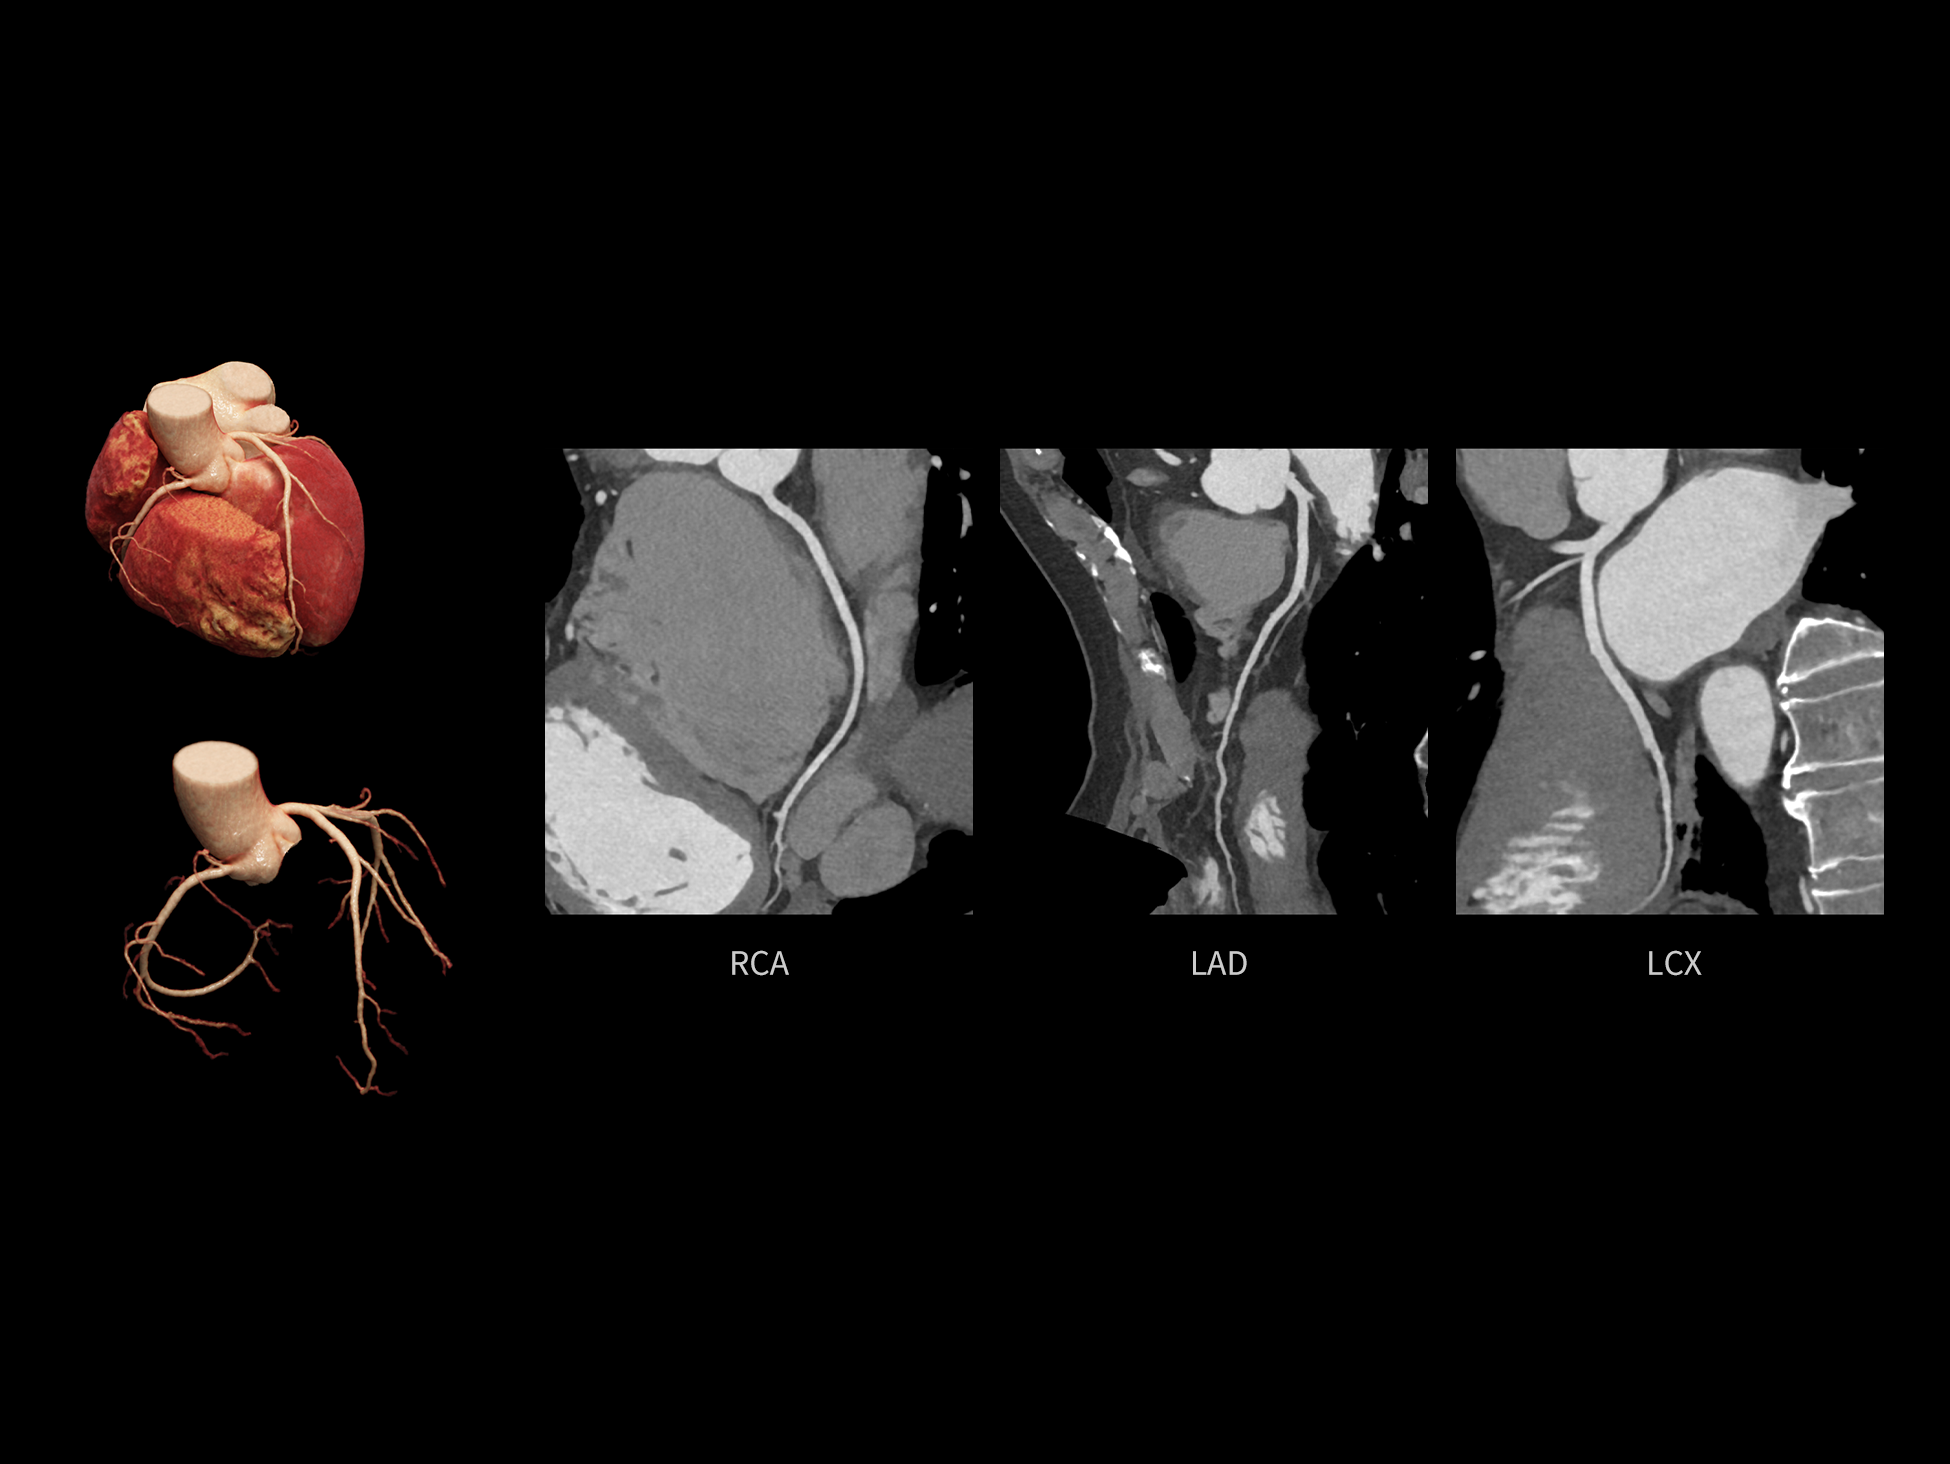

CardioCapture 2.0 可对心肌、瓣膜及心室等结构进行同步运动校正。基于深度学习的心脏精细分割,实现了更完整的心脏全局信息提取,能有效抑制全心运动伪影,显著提升心脏细节的清晰度与诊断可靠性。

全心结构运动校正